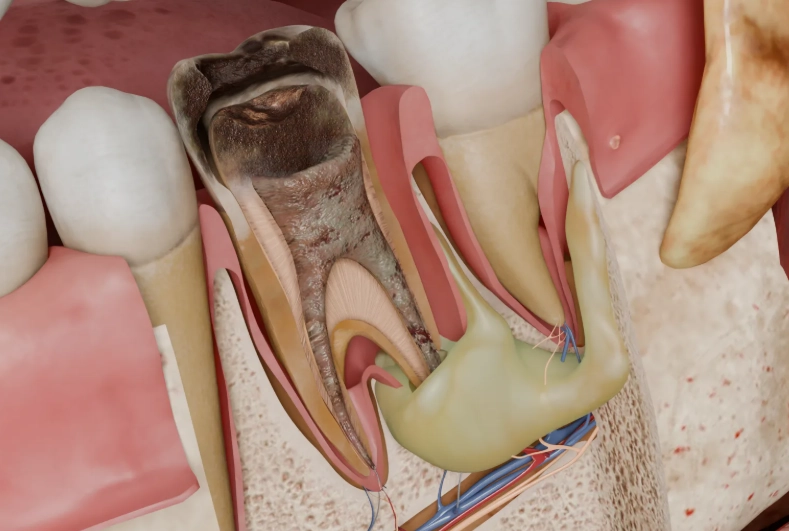

Inside every tooth is a tiny chamber and canals (the pulp) containing nerves, blood vessels, and connective tissue. When bacteria from a deep decay or crack invade this space, they cause an infection (pulpitis). If left alone, the infection kills the pulp and moves out through the tiny hole at the root tip.

Now it's in your jawbone. Your immune system launches a massive attack, sending white blood cells to fight. This battle—bacteria vs. immune cells—creates pus (a thick fluid of dead cells and bacteria).

Bone is hard. It doesn't stretch. So as this pus-filled sac grows at the root tip, it creates intense pressure. That pressure compresses the nerve fibers still in the bone and the periodontal ligament (the tiny shock absorbers holding your tooth in place).

Pressure on nerves = intense, localized pain.

It's like blowing up a balloon in a confined box. Something's gotta give. Eventually, the pus may erode through the bone and drain into the gums (creating that gum boil), which can temporarily relieve the pressure and pain. But the infection factory at the root tip is still running.